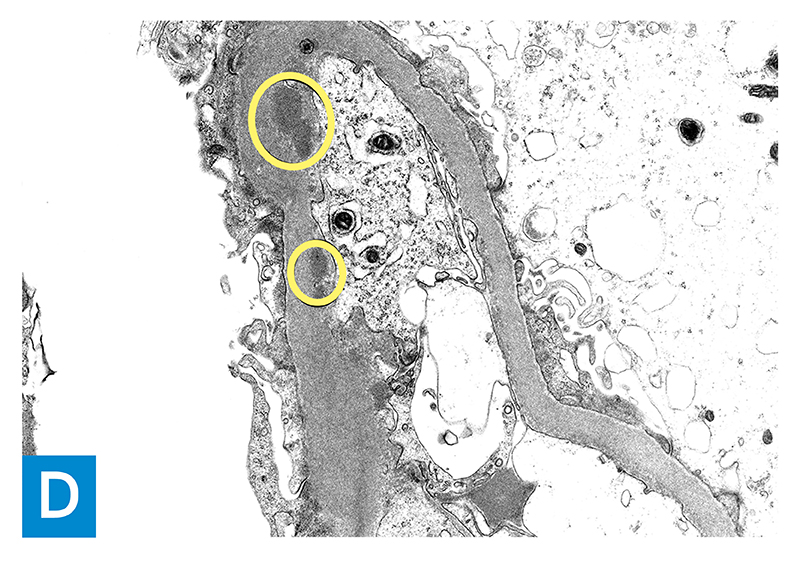

Figure 1D: Electron microscopy (12,000× magnification) showing granular immune complex deposits (circled) in the subendothelial location of a glomerular capillary loop basement membrane.